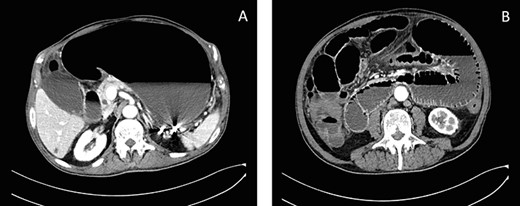

Plain abdomen radiography was performed at the ED and showed distended stomach and small bowel with air-fluid levels (Fig. 1). No free gas in the peritoneal cavity was seen. A contrast-enhanced CT scan revealed a huge gastrectasia with liquids, small bowel distention due to a suspected adherent bridle. Some loops of the ileum showed emphysematous walls (Fig. 2). A minimal perihepatic liquid effusion was observed due to suffering bowel.

Axial CT scans of abdomen show gastrectasia with the NG tube just inserted (A) and a suspected image of bowel emphysematous walls (B).